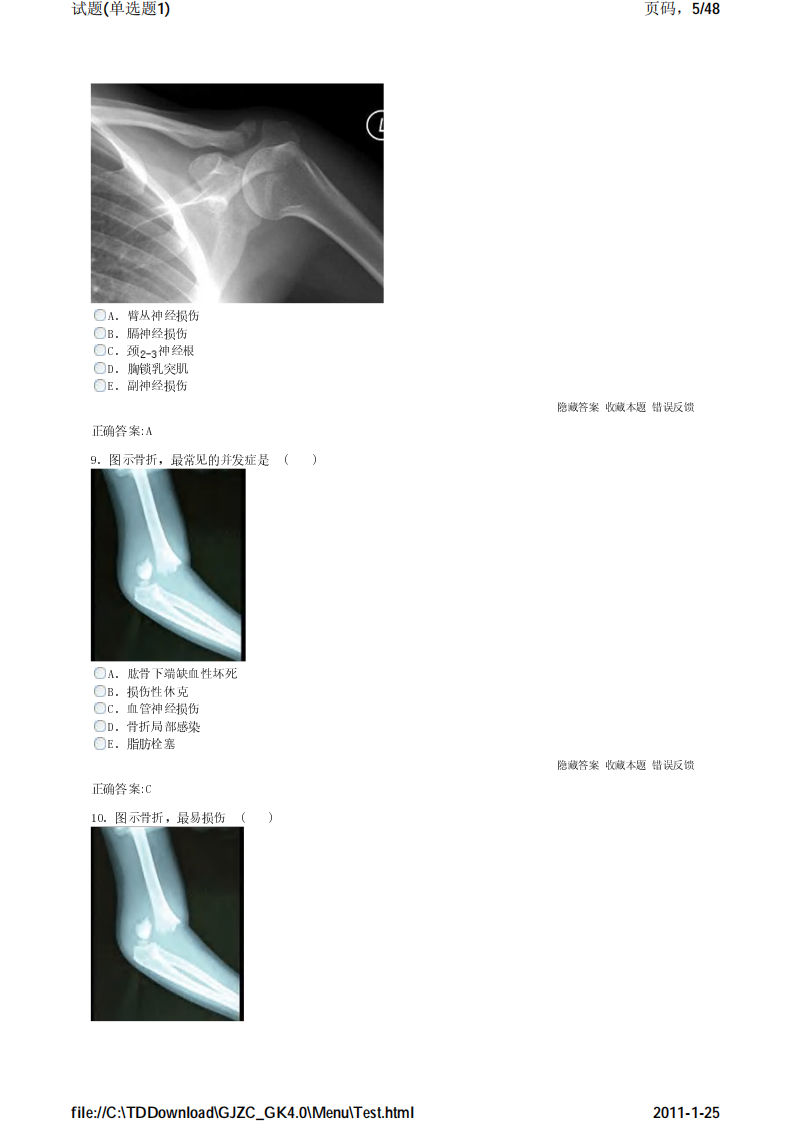

考试宝典 医学高级职称考试 骨科 单选题1.pdf

骨科